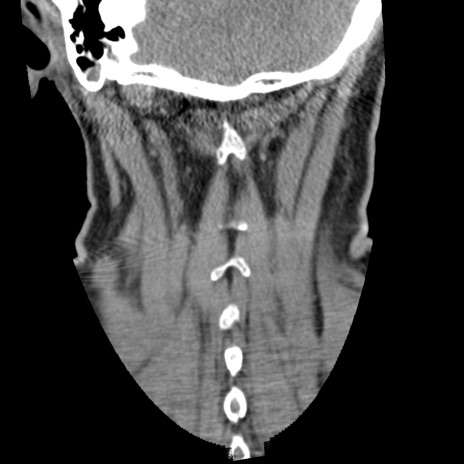

症例50 頚椎CT(冠状断像)

矢状断像